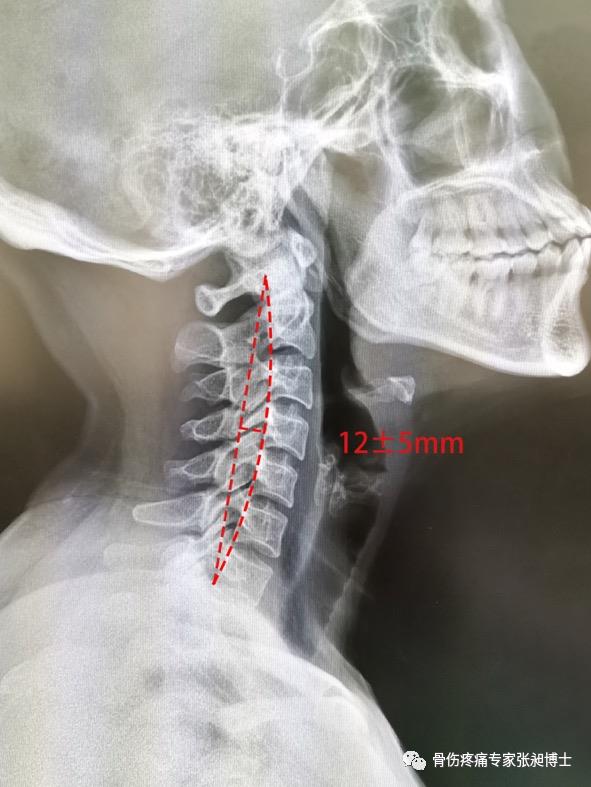

图1-1-2 颈椎的正常生理曲度

颈椎的生理曲度:

在颈椎X线的侧位片上,沿枢椎的齿状突后缘最高点与第七颈椎后下缘作一直线,将颈椎椎体后缘连一弧线。直线与弧线之间最宽处的距离正常值为12mm±5mm。